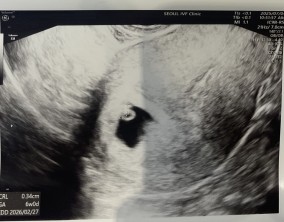

설렘과 불안의 시간을 지나 찾아온 선물

서울IVF여성의원의 난임 치료는 과정 하나하나가 체계적이고 세심하다는 인상을 받았습니다. 이유정 원장님과 간호사 분들께 치료 단계마다 충분한 설명을 들을 수 있어 불안이 많…